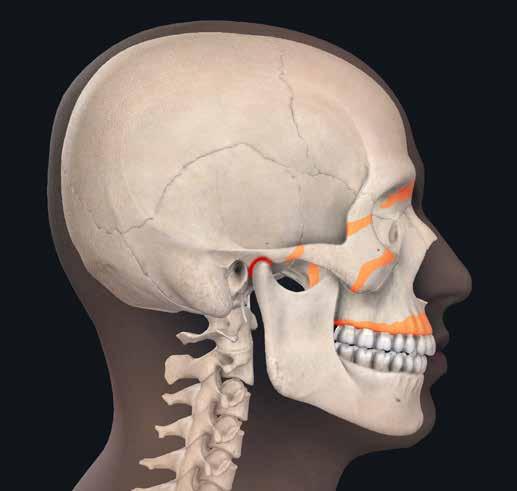

62-68 > Open-bite da abitudine viziata: succhiamento protratto del dito in una bimba di sette anni. Notare bene come il succhiamento protratto del dito determini la spinta indietro della mandibola, l’iposviluppo trasversale del mascellare superiore e, quindi, il conseguente open-bite grave, spesso aggravato anche dall’aumento della divergenza facciale.

69 > Centri di crescita: sono le aree rappresentate in arancione che rappresentano campi di crescita molto attivi, quali le suture craniche e facciali, i condili mandibolari, le tuberosità mascellari, i processi alveolari, le sincondrosi della base cranica. La crescita delle ossa non si verifica tuttavia soltanto in queste zone; tutti campi di crescita interni ed esterni di un osso partecipano di volta in volta al processo.

70, 71 > Centri di Crescita del mascellare superiore: processi di apposizione e di riassorbimento osseo determinano la crescita del mascellare in direzione posteriore.

Contemporaneamente il mascellare superiore viene spostato in avanti.

Nella zona delle giunzioni articolari si origina in tal modo lo spazio necessario per processi di apposizione ossea. Nella dislocazione primaria, il processo di dislocazione si svolge sempre in direzione

opposta al vettore di crescita ossea

(la figura 72

rappresenta siti di crescita cranio/facciale durante la vita dell’individuo.

La 73 rappresenta siti di crescita in corrispondenza del mascellare superiore e della base cranica).